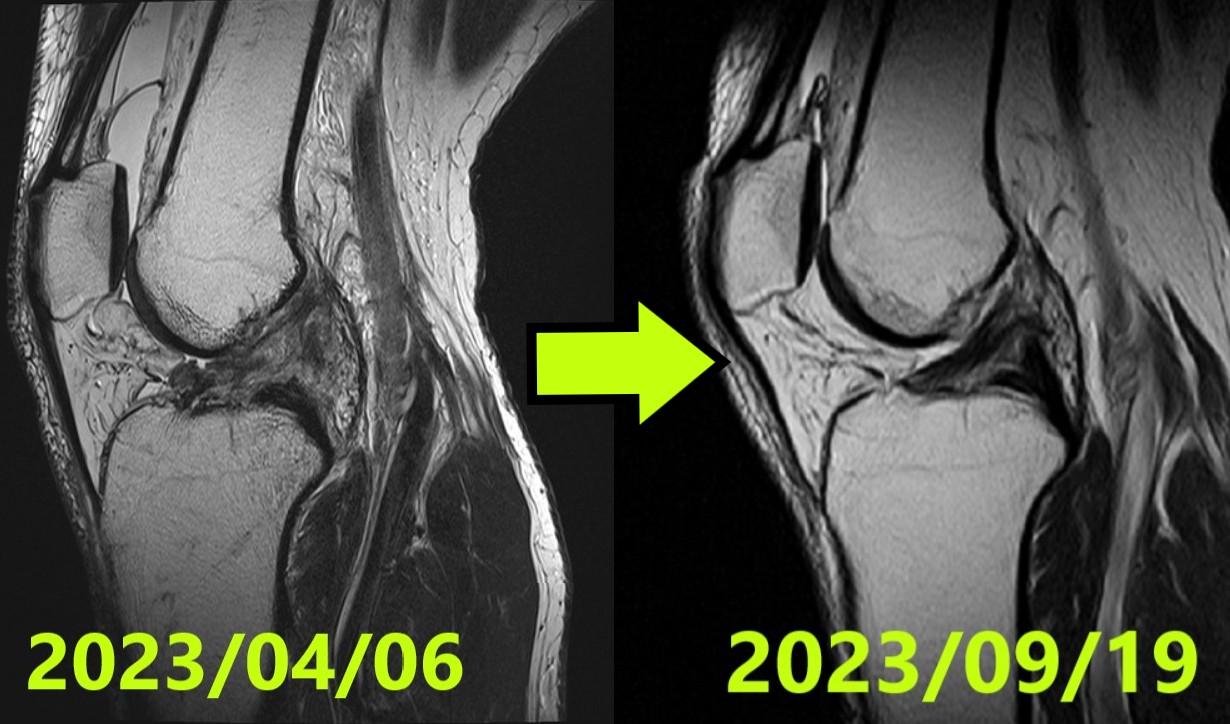

Caso di Guarigione Naturale LCA #50: Rigenerazione Perfetta (ACLOAS Grado 0) da una Grave Rottura Ihara Tipo IV

Rottura completa del legamento crociato anteriore (LCA) avvenuta durante un atterraggio in snowboard. Secondo una rigorosa procedura di consenso tra tre specialisti indipendenti, la diagnosi iniziale era Ihara Tipo IV (la rottura più grave e complessa). Il paziente ha appreso immediatamente la “rotazione esterna completa dell’anca” durante la consulenza online per gli Evo-Devo Exercise. Attraverso una gestione rigorosa dell’allineamento (tutore 0–30° / ≤3.000 passi al giorno) e programmi di esercizi costanti 3 volte al giorno, la risonanza magnetica finale ha ottenuto il massimo punteggio possibile: ACLOAS Grado 0 (rigenerazione della struttura normale del legamento). Il paziente è tornato con successo alle attività quotidiane e ha iniziato il ritorno graduale allo sport.

Valutazione Iniziale (MRI #1)

- Data: 6 aprile 2023

- Diagnosi: Rottura completa LCA ginocchio sinistro

- Classificazione Ihara: IV (Grado 4) — Confermata dal consenso di 3 specialisti indipendenti

Valutazione MRI Finale (~5 mesi)

- Data: 19 settembre 2023

- Valutazione: ACLOAS Grado 0 (rigenerazione della struttura normale) — Confermato dal consenso di 3 specialisti indipendenti

- Risultato: Il legamento precedentemente rotto ha ottenuto una rigenerazione di alta qualità con una morfologia identica a un legamento sano

- MRI #1 (06/04/2023): Ihara IV — confermata come grave rottura completa da 3 specialisti

- MRI #2 (19/09/2023): ACLOAS 0 — confermata come rigenerazione di alta qualità da 3 specialisti